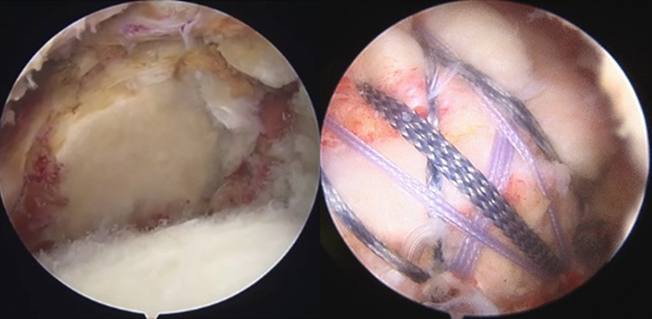

腱板断裂においては、鏡視下手術を中心に行っております。腱板断裂は、転倒などの外傷性のものと、日常の負荷、動作時のすり減りなどで変性し断裂するものがあります。腱板断裂部の断裂サイズの大きい大・広範囲断裂といわれる症例においては、腱断端部の緊張を抑えて修復する、Debeyre-patte変法(筋前進術)などを行っております。

- 反復性肩関節脱臼に対しては、スポーツ内容や仕事内容などによって方針を検討し、関節窩や上腕骨の骨欠損が大きいもの、コンタクトスポーツなどの再脱臼リスクの高い症例に関しては、関節窩の骨欠損部を補填するため、人工骨を用いて鏡視下Bankart修復術を施行し、再脱臼率の低減を目指しています。